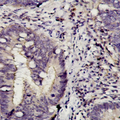

本研究探讨MTHFR基因多态性与P170糖蛋白在大肠癌中表达的相关性。采集承德汉族55例大肠癌患者标本,采用PCR-RFLP技术检测大肠癌组织中MTHFR基因C677T的基因型、同时用免疫组化方法检测P170糖蛋白在大肠癌中的表达情况,最后 采用统计学方法,得出结论:大肠癌组织中P170糖蛋白的表达与MTHFR基因677T/T基因型负相关,可能成为大肠癌化疗敏感性的有效指标。

目的:研究亚甲基四氢叶酸还原酶(methylenetetrahydrofolate reductase,MTHFR)基因多态性与多药耐药基因蛋白(P170糖蛋白)在大肠癌组织中表达的相关性。 背景: 大肠癌为结肠癌和直肠癌的总称,是我国常见的消化道恶性肿瘤之一,死亡率较高且呈逐年上升趋势。研究证实,P170糖蛋白是造成大肠癌化疗失败的主要原因之一。目前已证明,MDR1基因及其表达产物P170糖蛋白过度表达所介导的对抗癌药物的多药耐药性是影响化疗敏感性的重要因素。流行病学和试验研究提示叶酸缺乏及叶酸代谢异常和结直肠肿瘤发病风险升高有关,亚甲基四氢叶酸还原酶(MTHFR)是调节叶酸代谢的关键酶,MTHFR C677T基因多态及饮酒影响叶酸代谢,从而影响结直肠肿瘤的发病风险,与大肠癌的关系密切。 方法:收集2009.06--2009.12在承德某医院住院并行手术的55例汉族患者的大肠癌组织标本, 用聚合酶链反应-限制性片段长度多态性技术(PCR-RFLP)检测大肠癌组织中MTHFR基因C677T的基因型;同时用免疫组化方法检测P170糖蛋白在不同分化程度大肠癌组织中的表达情况。 结果: 55例大肠癌组织中,高分化、中分化、低分化中P170糖蛋白的阳性表达率分别为44.4%(5/9)、52.2%(19/40)、33.3%(4/6)。P170在大肠癌组织中的表达与大肠癌的分化程度无相关性(X2=0.86,P>0.05),其中MTHFR C677T T/T基因型的大肠癌组织中P170糖蛋白阳性表达率显著低于C/T基因型(X2=7.464,P<0.05);又显著低于C/C基因型(X2=6.875,P<0.05);C/T基因型和C/C基因型之间大肠癌组织中P170糖蛋白阳性表达率没有显著性差异(X2=0.016,P>0.05)。 结论:MTHFR基因C677T T/T基因型的大肠癌组织中P170糖蛋白的表达明显低于C/T型和C/C型, MTHFR基因C677T T/T基因型可能成为大肠癌化疗敏感性的有效指标,为指导临床医生进行个体化化疗提供理论依据。

目的:研究亚甲基四氢叶酸还原酶(MTHFR)基因多态性与P170糖蛋白在大肠癌组织中表达的相关性。 方法:收集2009.06--2009.12在承德某医院住院并行手术的55例汉族患者的大肠癌组织标本, 用PCR-RFLP检测大肠癌组织中MTHFR基因C677T的基因型;同时用免疫组化方法检测P170糖蛋白在不同分化程度大肠癌组织中的表达情况。 结果: 55例大肠癌组织中,高分化、中分化、低分化中P170糖蛋白的阳性表达率分别为44.4%(5/9)、52.2%(19/40)、33.3%(4/6)。P170糖蛋白在大肠癌组织中的表达与大肠癌的分化程度无相关性(X2=0.86,P>0.05),其中MTHFR C677T T/T基因型P170糖蛋白阳性表达率显著低于C/T基因型(X2=7.464,P<0.05);又显著低于C/C基因型(X2=6.875,P<0.05);C/T基因型和C/C基因型之间无显著性差异(X2=0.016,P>0.05)。 结论:大肠癌组织中P170糖蛋白的表达与MTHFR基因677T/T基因型负相关,可为指导临床医生进行个体化化疗提供理论依据。